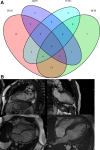

Background: Although left ventricular noncompaction (LVNC) has been associated with an increased risk of adverse cardiovascular events, the accurate incidence of cardiovascular morbidity and mortality is unknown. We, therefore, aimed to assess the incidence rate of LVNC-related cardiovascular events.

Results: We identified 28 eligible studies enrolling 2501 LVNC patients (mean age, 46 years; male/female ratio, 1.7). After a median follow-up of 2.9 years, the pooled event rate for cardiovascular mortality was 1.92 (95% CI, 1.54-2.30) per 100 person-years. LVNC patients had a similar risk of cardiovascular mortality compared with a dilated cardiomyopathy control group (odds ratio, 1.10 [95% CI, 0.18-6.67]). The incidence rates of all-cause mortality, stroke and systemic emboli, heart failure admission, cardiac transplantation, ventricular arrhythmias, and cardiac device implantation were 2.16, 1.54, 3.53, 1.24, 2.17, and 2.66, respectively, per 100 person-years. Meta-regression and subgroup analyses revealed that left ventricular ejection fraction, not the extent of left ventricular trabeculation, had an important influence on the variability of incidence rates. The risks of thromboembolism and ventricular arrhythmias in LVNC patients were similar to dilated cardiomyopathy patients. However, LVNC patients had a higher incidence of heart failure hospitalization than dilated cardiomyopathy patients.

Conclusions: Patients with LVNC carry a similar cardiovascular risk when compared with dilated cardiomyopathy patients. Left ventricular ejection fraction-a conventional indicator of heart failure severity, not the extent of trabeculation-appears to be an important determinant of adverse outcomes in LVNC patients. Registration: https://www.crd.york.ac.uk/PROSPERO/ Unique identifier: CRD42018096313.